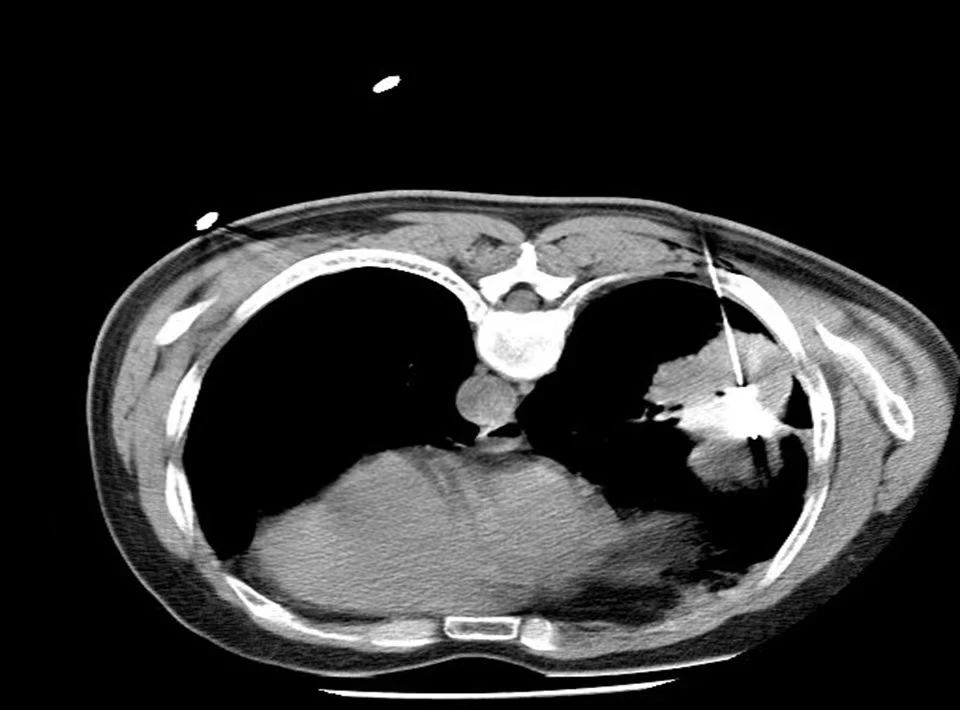

患者張大爺,85歲,肺占位性病變(左下肺)約1.1cm,伴有心臟病、高血壓,一年前體檢時無意中發(fā)現(xiàn)左下肺有一約3mm大小磨玻璃結節(jié),未予重視。近日,張大爺因胸痛到徐州市中醫(yī)院住院治療。復查胸部CT,發(fā)現(xiàn)左下肺結節(jié)已增大至約1.1cm大小。

徐州市中醫(yī)院胸外科術前和放射科同事們一起為張大爺詳細規(guī)劃進針路線,術中對病灶進行精準穿刺,成功避開重要血管和器官。使用功率50w3分鐘消融腫瘤,同步活檢取病理;后續(xù)使用功率40w2分鐘進行腫瘤消融,術后影像顯示消融范圍全部覆蓋腫瘤病灶。整個微波消融手術全程耗時約半小時左右。